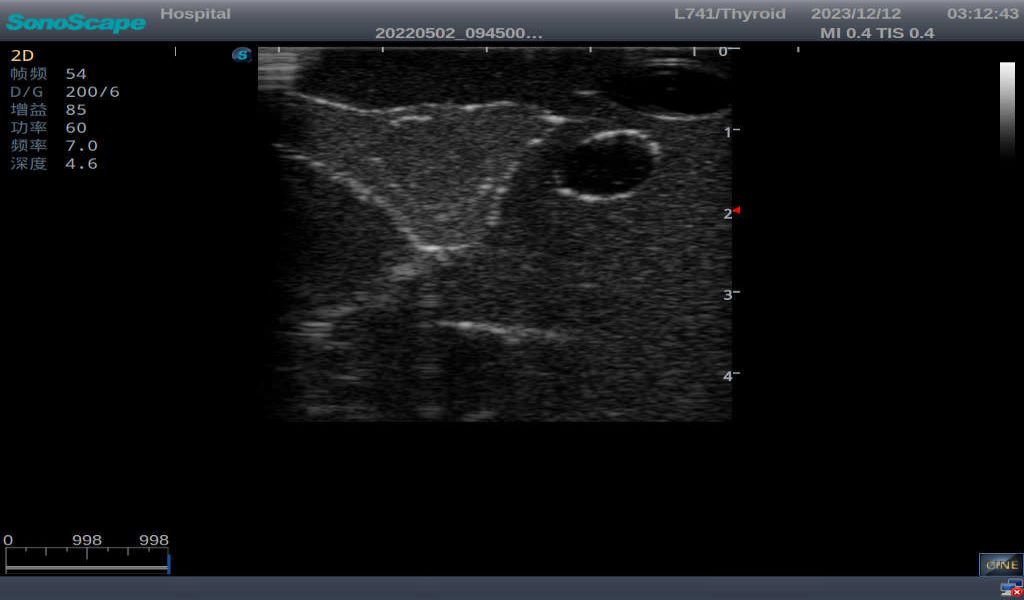

3)       It comes with four (4) thyroid modules and can show five (5) ultrasonic images: normal thyroid, thyroid adenoma, thyroid cancer, nodular goiter, thyroid cyst

Thyroid adenoma with well-defined border and smooth uniform halo